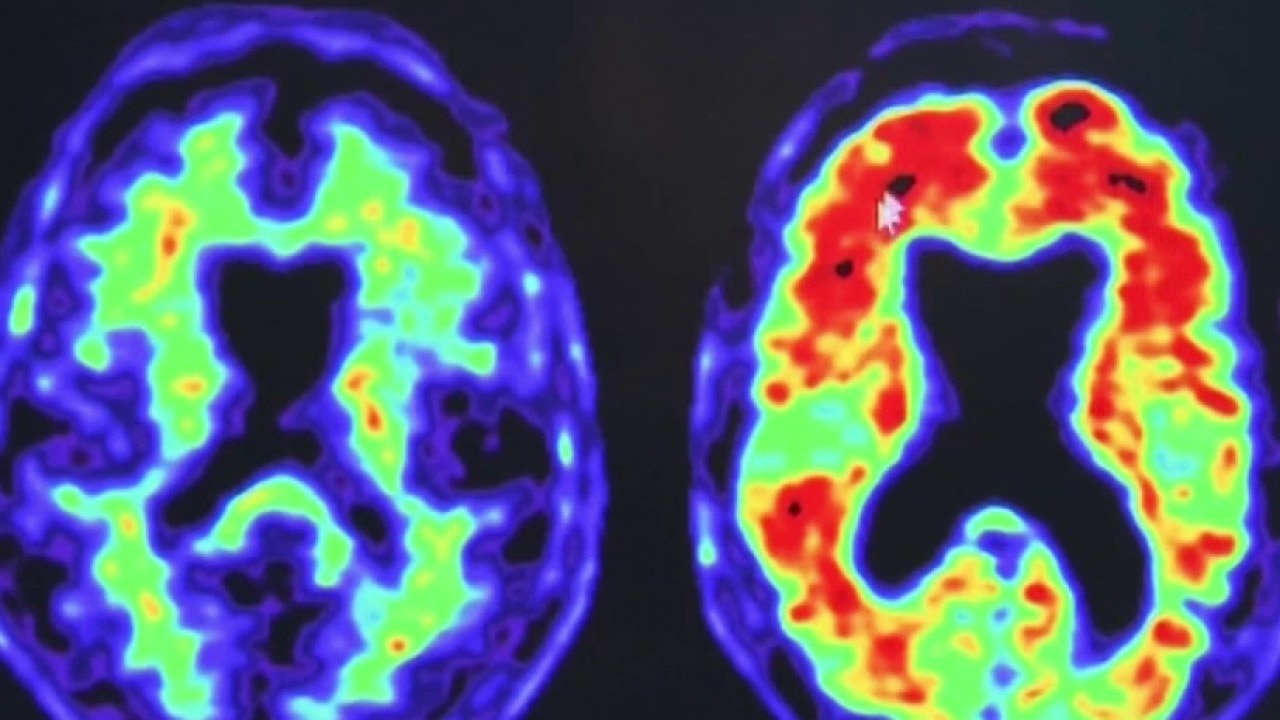

Your sleep may reveal early signs of dementia risk, study finds

A new study from UCSF suggests your brain may be aging faster than you think, and the warning signs could show up while you sleep.